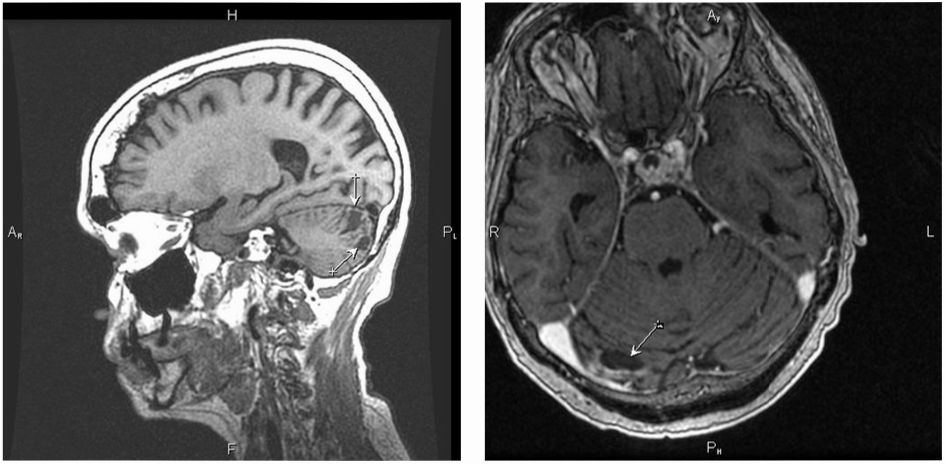

С апреля 2021 г. назначена терапия алпелисибом в комбинации с фулвестрантом (в качестве 7-й линии ЭТ). По результатам ПЭТ/ КТ от августа 2021 г. на фоне терапии алпелисибом отмечена положительная динамика – ЧО. С октября по декабрь 2021 г. пациентка прервала терапию алпелисибом в связи с коронавирусной инфекцией. По данным ПЭТ/КТ от декабря 2021 г. в сравнении с ПЭТ/КТ от августа 2021 г. отмечена отрицательная динамика опухолевого процесса. Учитывая ограниченность возможных лекарственных опций, принято решение о возобновлении терапии алпелисибом в комбинации с фулвестрантом в прежнем режиме. На фоне терапии отмечено клиническое улучшение общего состояния пациентки. По данным ПЭТ/КТ от июня 2022 г. продолжалась стабилизация заболевания: в динамике сохранялись множественные очаги в легких с умеренным снижением активности фтордезоксиглюкозы, в сегменте SIV левого легкого очаг размерами 13×10 мм, SUVmax 3,74 (ранее 16×10 мм, SUVmax 4,74), в сегменте SIX правого легкого до 17×14 мм, SUVmax 5,01 (ранее SUVmax 5,11), в динамике очаг в левой плечевой кости стабилен SUVmax 2,21 (ранее 2,35), очаг в левой бедренной кости SUVmax 4,83 (ранее 3,91), очаг в правой подвздошной кости SUVmax 2,6 (ранее 4,73). Терапию продолжили, при контрольных исследованиях от 15 декабря 2022 г. и 17 июня 2023 г. получены ЧО, 20 ноября 2023 г. ЧО сохранялся. Суммарная продолжительность лечения алпелисиб + фулвестрант составила 33 мес (рис. 6, 7).

Рис. 7. ЧО на терапию алпелисиб + фулвестрант в головном мозге: в веществе правого полушария мозжечка сохраняются два очага кистозной структуры, количеством 5, неправильной формы, с наличием солидного компонента по периферии, глыбчато накапливающего контрастное вещество, в виде неравномерно утолщенного до 10 мм ободка, без наличия перифокального отека, с уменьшением размеров 35×36→24×14 мм и 16×25→11×20 мм.

Fig. 7. PR for alpelisib + fulvestrant therapy in the brain: in the right cerebellar hemisphere, there are two cystic lesions of irregular shape, with a solid peripheral component and lumpy uptake of the contrast agent, observed as an unevenly thickened rim up to 10 mm, without perifocal edema; their size decreased from 35×36 mm to 24×14 mm and from 16×25 to 11×20 mm.